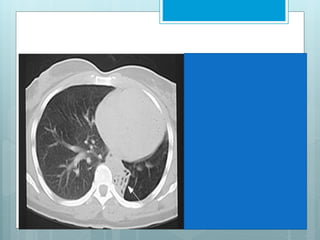

•Increased triangular opacity

within the RLL

•Commonly seen with loss of the

right hemi-diaphragm